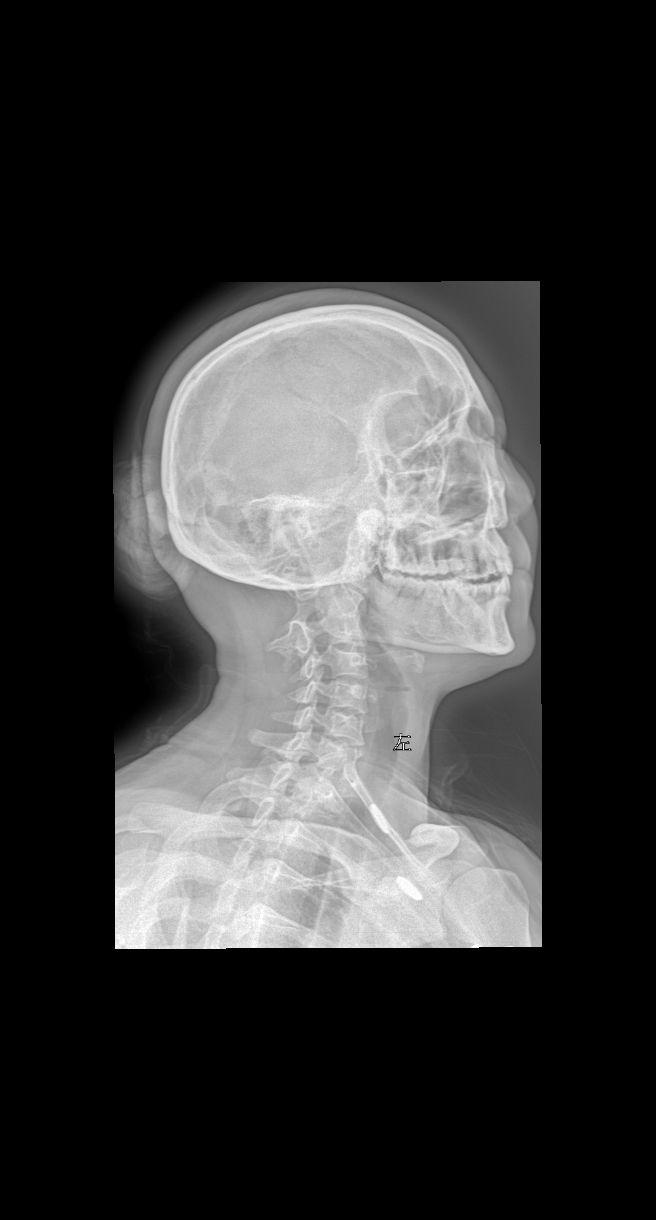

来张颈椎四位片瞅瞅大家怎么拍的